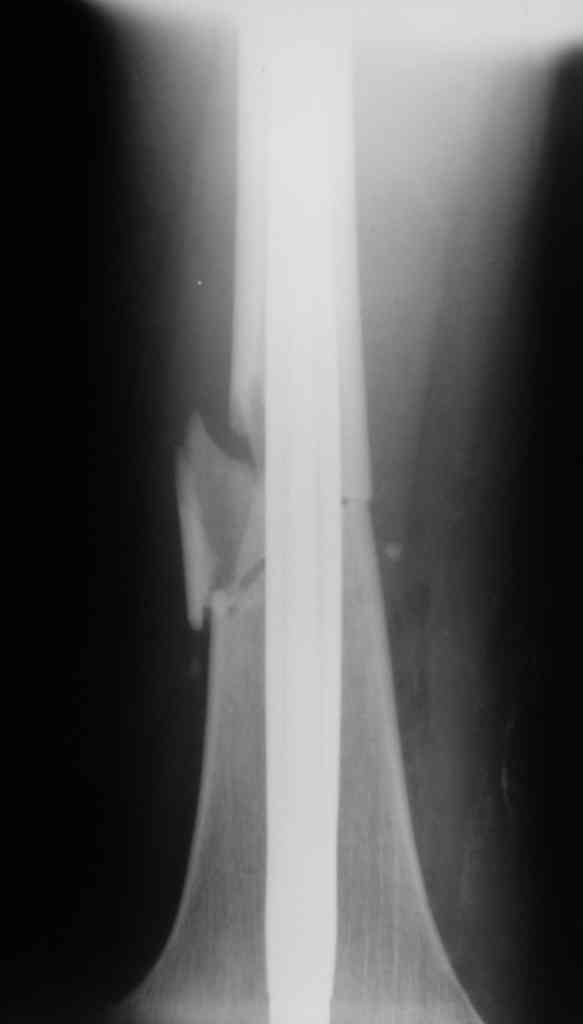

Дорогой Александр. Имею скромный опыт использования системы Fixion при переломах плеча, бедра и тибии. Всего 18 наблюдений с сентября 2006 г. Результаты отличные. Гвоздь индивидуален для каждого медуллярного канала. Легко имплантируется как в узкий, так и в деформированный канал. Это позволяет применять метод интрамедулярного остеосинтеза без ненужных потерь времени операции, флюороскопии и реально снижает крвопотерю и операционный риск. Удаление происходит без проблем. Особенно интересны больные с ипсилатеральными переломами бедра и голени.

В отношении ранней нагрузки при спиральных переломах лучше не торопиться. По данному случаю необходимо достигнуть исчезновения щели между штифтом и внутреним кортексом по Rg. А так картинка прекрасная - и длина сегмента и репозиция. Можно поздравить, коллега!